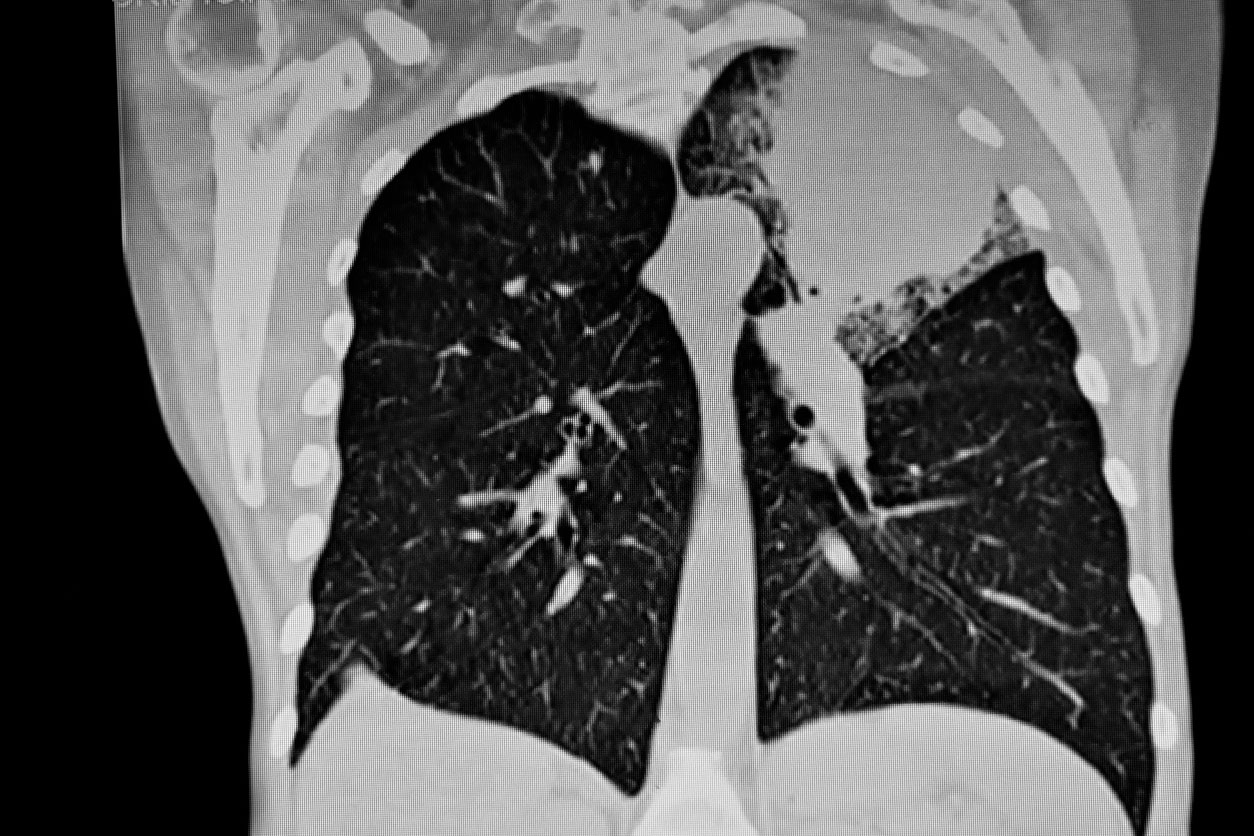

The ECLS study involved 12,215 individuals who were either smokers or ex-smokers and at high risk of developing lung cancer. Participants were randomised either to receive a new intervention or to receive the current standard of care. For those receiving the EarlyCDT-Lung® test, researchers were able to check if the individual’s immune system had produced antibodies against cancer antigens (protein) which could be detected in their blood. If the test was positive the participants were scheduled to have CT scans of the chest every six months for two years unless a lung cancer was diagnosed within the two-year period.

ECLS is the first trial conducted worldwide as a phase IV evaluation of a blood-based biomarker antibody panel for early detection of lung cancer. Body (CT) scanning has been the preferred method of detection of early stage lung cancer but this requires large imaging infrastructure, is costly and CT scans involve radiation exposure. The safety of screening patients with CT scans over many years, for example more than three years, with cumulative radiation exposure has not been assessed.